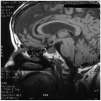

Se realizó un EEG que demostró brotes periódicos de supresión de gran persistencia que podrían ir a favor una lesión del troncoencefálo de grado moderado-intenso. Se solicitó una resonancia magnética cerebral que demostró la existencia de una masa intraselar de 1,5 cm, que ampliaba el tamaño de la silla turca y que realzaba de forma heterogénea con contraste, y no se identificó la hipófisis normal (fig. 1).

Figura 1. Resonancia magnética cerebral, en la que en la silla turca se evidencia una masa tumoral.